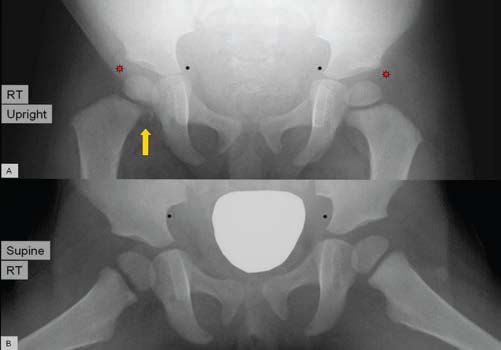

Nishit Patel, MD; Amir Raza, PA-C; Thomas R. Lewis, MD; Sandeep G. Prabhu, MD; Faridali G. Ramji, MD

A 19-month-old girl was brought into the orthopedic clinic by her parents for a chief concern of limping on her right leg for 9 days.